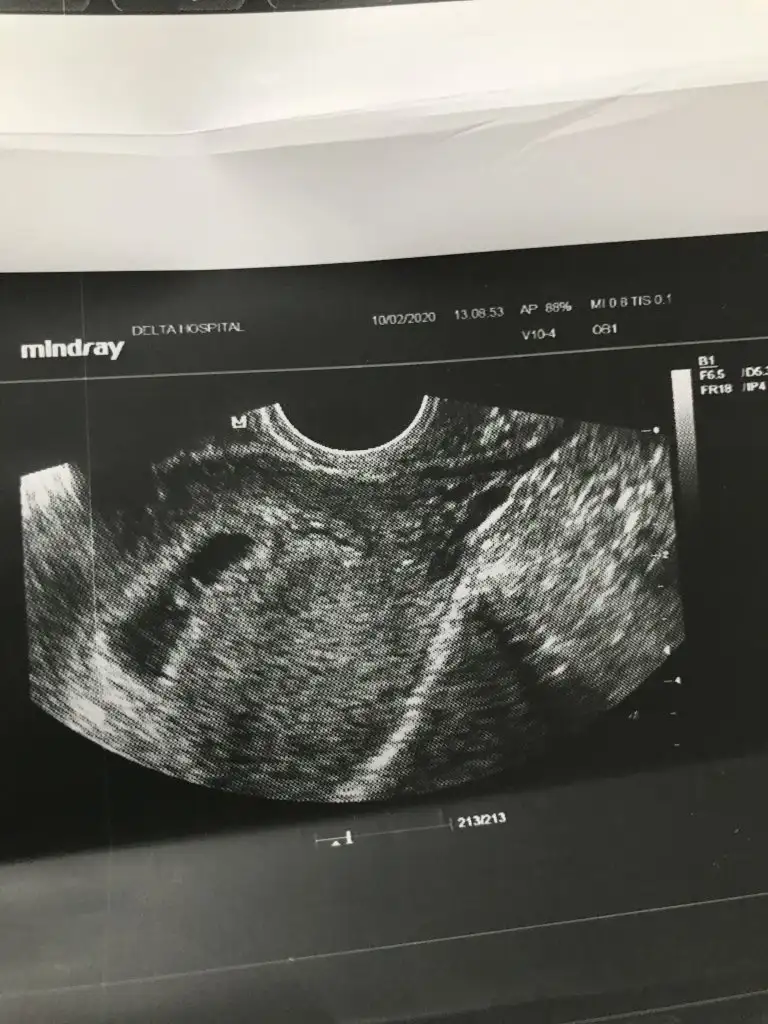

Merhaba cnm dün gittim Bi hastaneye cok güvenmediği m için devlet hastanesinde gittim ikiside kese dısında bsy göremedi Bi 10 mm diğeri 16 mm dediler kese için bnimde canm sıkıldı 6 haftalık bebek artıkgözükmesi gerekir Di cunkü bgn özel muayenehanesi olan Baska Bi doktora gittim hem bebeği gördüm hem kalp atısını duyduk cok garip walla 2 gündür kafam corba oldu bu nasıl iş anlamadım 350 TL muayene ücreti verince hersey görülüyor sanırımTamam canım güzel haberler ile gel inşallah